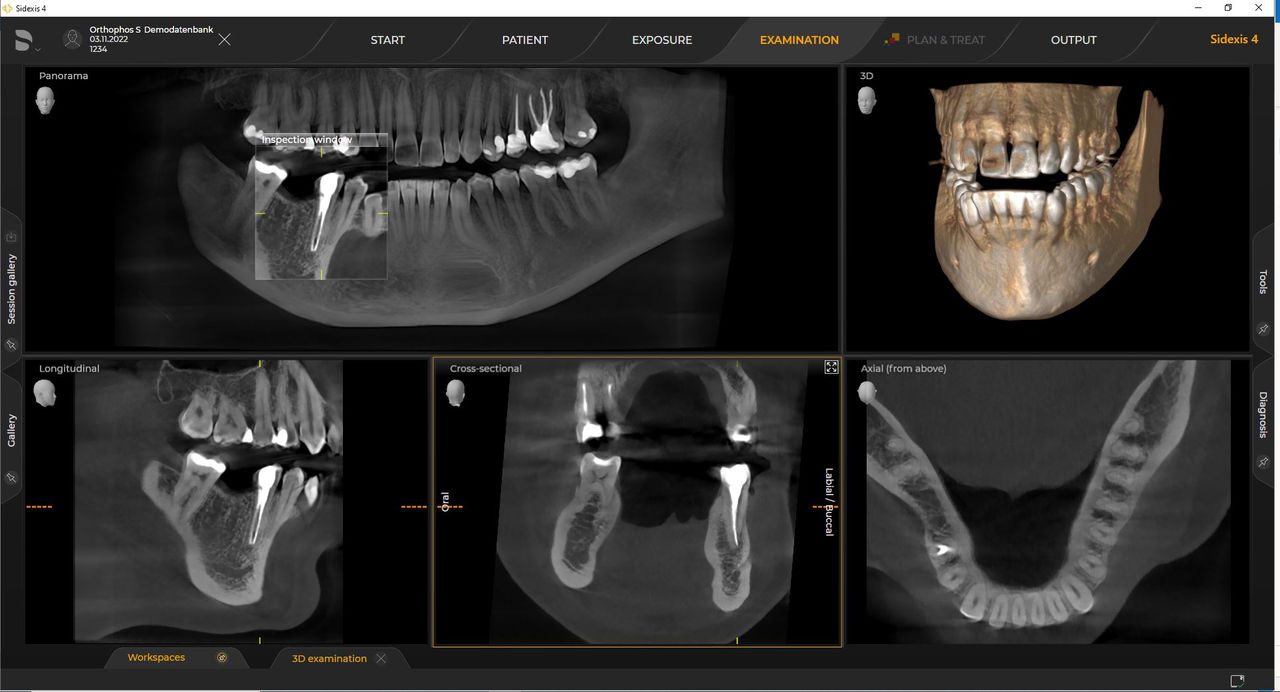

Con el modo de dosis baja inteligente 3D, obtiene imágenes 3D en el rango de dosis de una imagen radiológica 2D. En el modo HD (hasta 1400), las imágenes individuales se obtienen durante una única rotación y se convierten en un volumen 3D con hasta 80 μm para imágenes de bajo ruido en alta resolución.

Una amplia gama de tamaños de volumen para satisfacer sus diversas necesidades clínicas y de diagnóstico, desde Ø 5 x 5,5 cm hasta Ø 11 x 10 cm

Los requisitos siguen los del software de procesamiento de imágenes Sidexis 4 y Orthophos S. Para obtener más detalles, consulte los requisitos del sistema Sidexis 4 y los requisitos de instalación de Orthophos S.

Las unidades de radiología de Dentsply Sirona funcionan exclusivamente con Sidexis 4. Sin embargo, la migración de datos de Sidexis XG a Sidexis 4 es muy fácil. Sidexis 4 permite una experiencia digital completa con las últimas herramientas